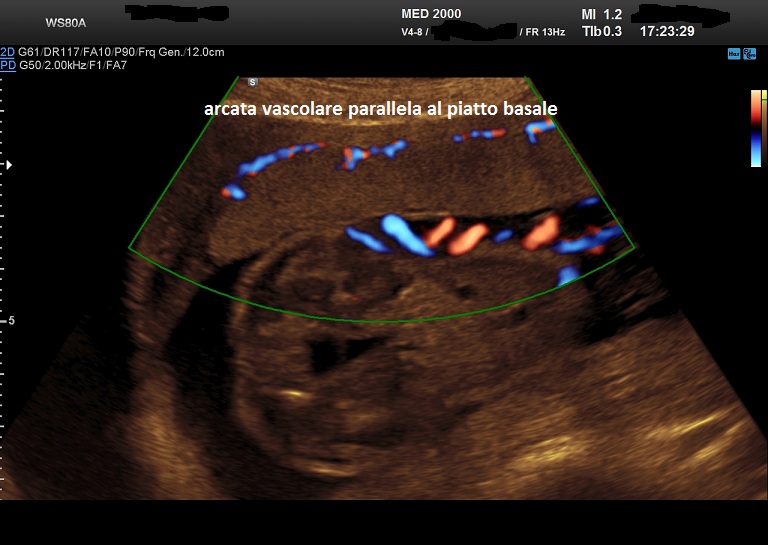

criteri ecografici color doppler

- l'arcata vascolare normalmente parallela al piatto basale perde questa caratteristica

- presenza di lacune vascolari placentari con flusso turbolento (velocità di picco sistolico > 15 cm./sec.)

- vascolarizzazione intraplacentare irregolare con vasi tortuosi confluenti

- ipervascolarizzazione dell'interfaccia sierosa-vescica